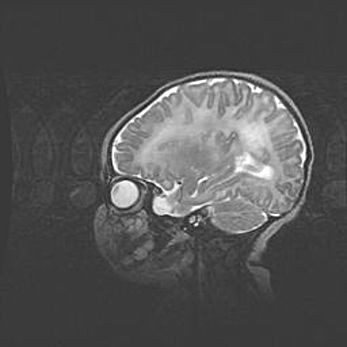

Множественные кисты обоих полушарий головного мозга, наибольшая из них в правой затылочной области. Ассиметричная атрофическая гидроцефалия.

Возраст: 7 месяцев

Вес: 5660 г

Пол: мужской

Окружность головы: 41,5 см

Срок гестации: 28-29 недель

Кисты головного мозга развиваются в результате многоочаговых некрозов вещества мозга и возникают вследствие перенесенной перинатальной инфекции, менингитов, энцефалитов, асфиксии, родовой травмы, расстройств мозгового кровообращения различного генеза. Образованию кист в веществе головного мозга плодов и новорожденных способствуют такие факторы, как высокое содержание в нем воды, недостаточная (или отсутствие) миелинизация и слабая астроглиальная реакция на повреждение.

Кисты могут сочетаться с гидроцефалией и другими поражениями головного мозга.